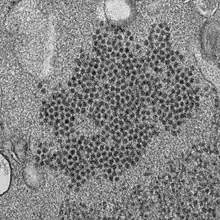

Transmission electron micrograph of enterovirus D68 virus particles[17] -

- ↑ "Enterovirus D68 Virus Particles". NIAID/CDC. 13 May 2024. Archived from the original on 6 July 2024. Retrieved 5 July 2024.